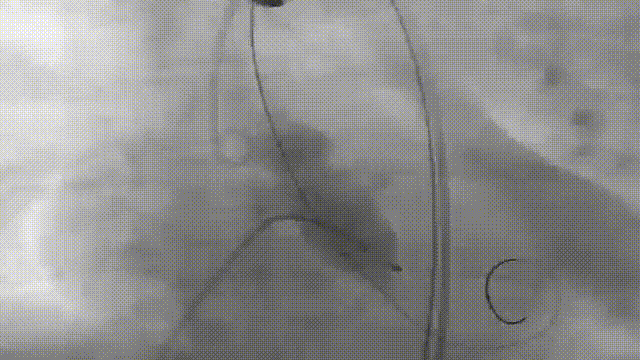

第一次释放

第二次释放

反复造影确认冠脉风险